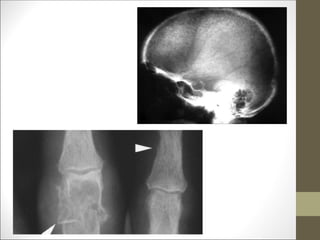

Bone Manifestations

• Rarely PHPT bone disease – osteitis fibrosa cystica- <5 percent

subperiosteal resorption